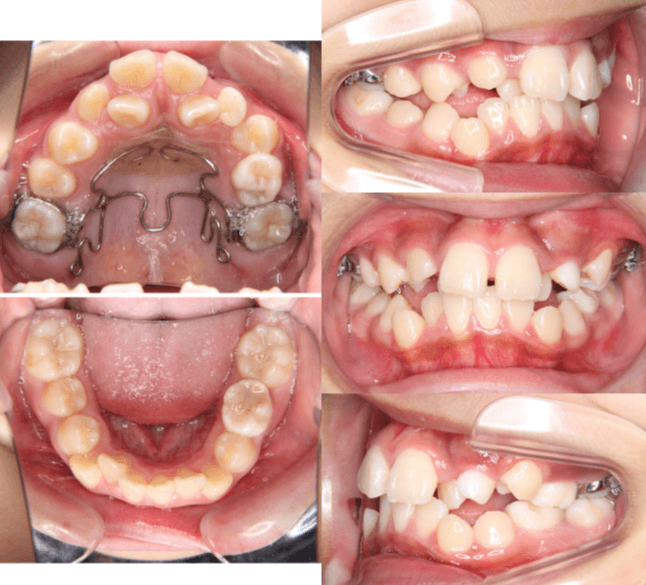

早期矯正治療 埋伏歯症例②

主訴 | 上顎前歯の位置異常に不安を抱え、歯並びと将来的な咬合状態を整える目的で来院された患者様です。 特に左側の前歯(中切歯および側切歯)の萌出が確認できないことがきっかけとなりました。 |

---|---|

診断結果 | 8歳3か月の男児。 左上1番(中切歯)と左上2番(側切歯)が埋伏し、発育方向にも異常が認められました。加えて、一部先天性欠如も確認されており、歯列全体の成長に影響を及ぼす可能性があると診断されました。 |

治療内容 |

|

治療後の経過 | 動的治療後は3〜4か月ごとの定期検診を行い、上下顎の骨の成長や第二大臼歯の萌出状況を確認しながら、本格的な矯正治療を行う |

治療期間 | 動的治療期間:約5年10か月 |

治療費用 | 460,000円(税別) |